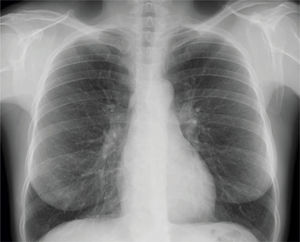

Tras estos hallazgos, se coloca tubo de drenaje torácico y es ingresada en el servicio de cirugía torácica. Tras 24 horas, presenta resolución completa del neumotórax, por lo que se pinza el tubo de drenaje (fig. 2). En la radiografía de control de 24 horas persiste resolución del cuadro, por lo que se retira dicho tubo (fig. 3).